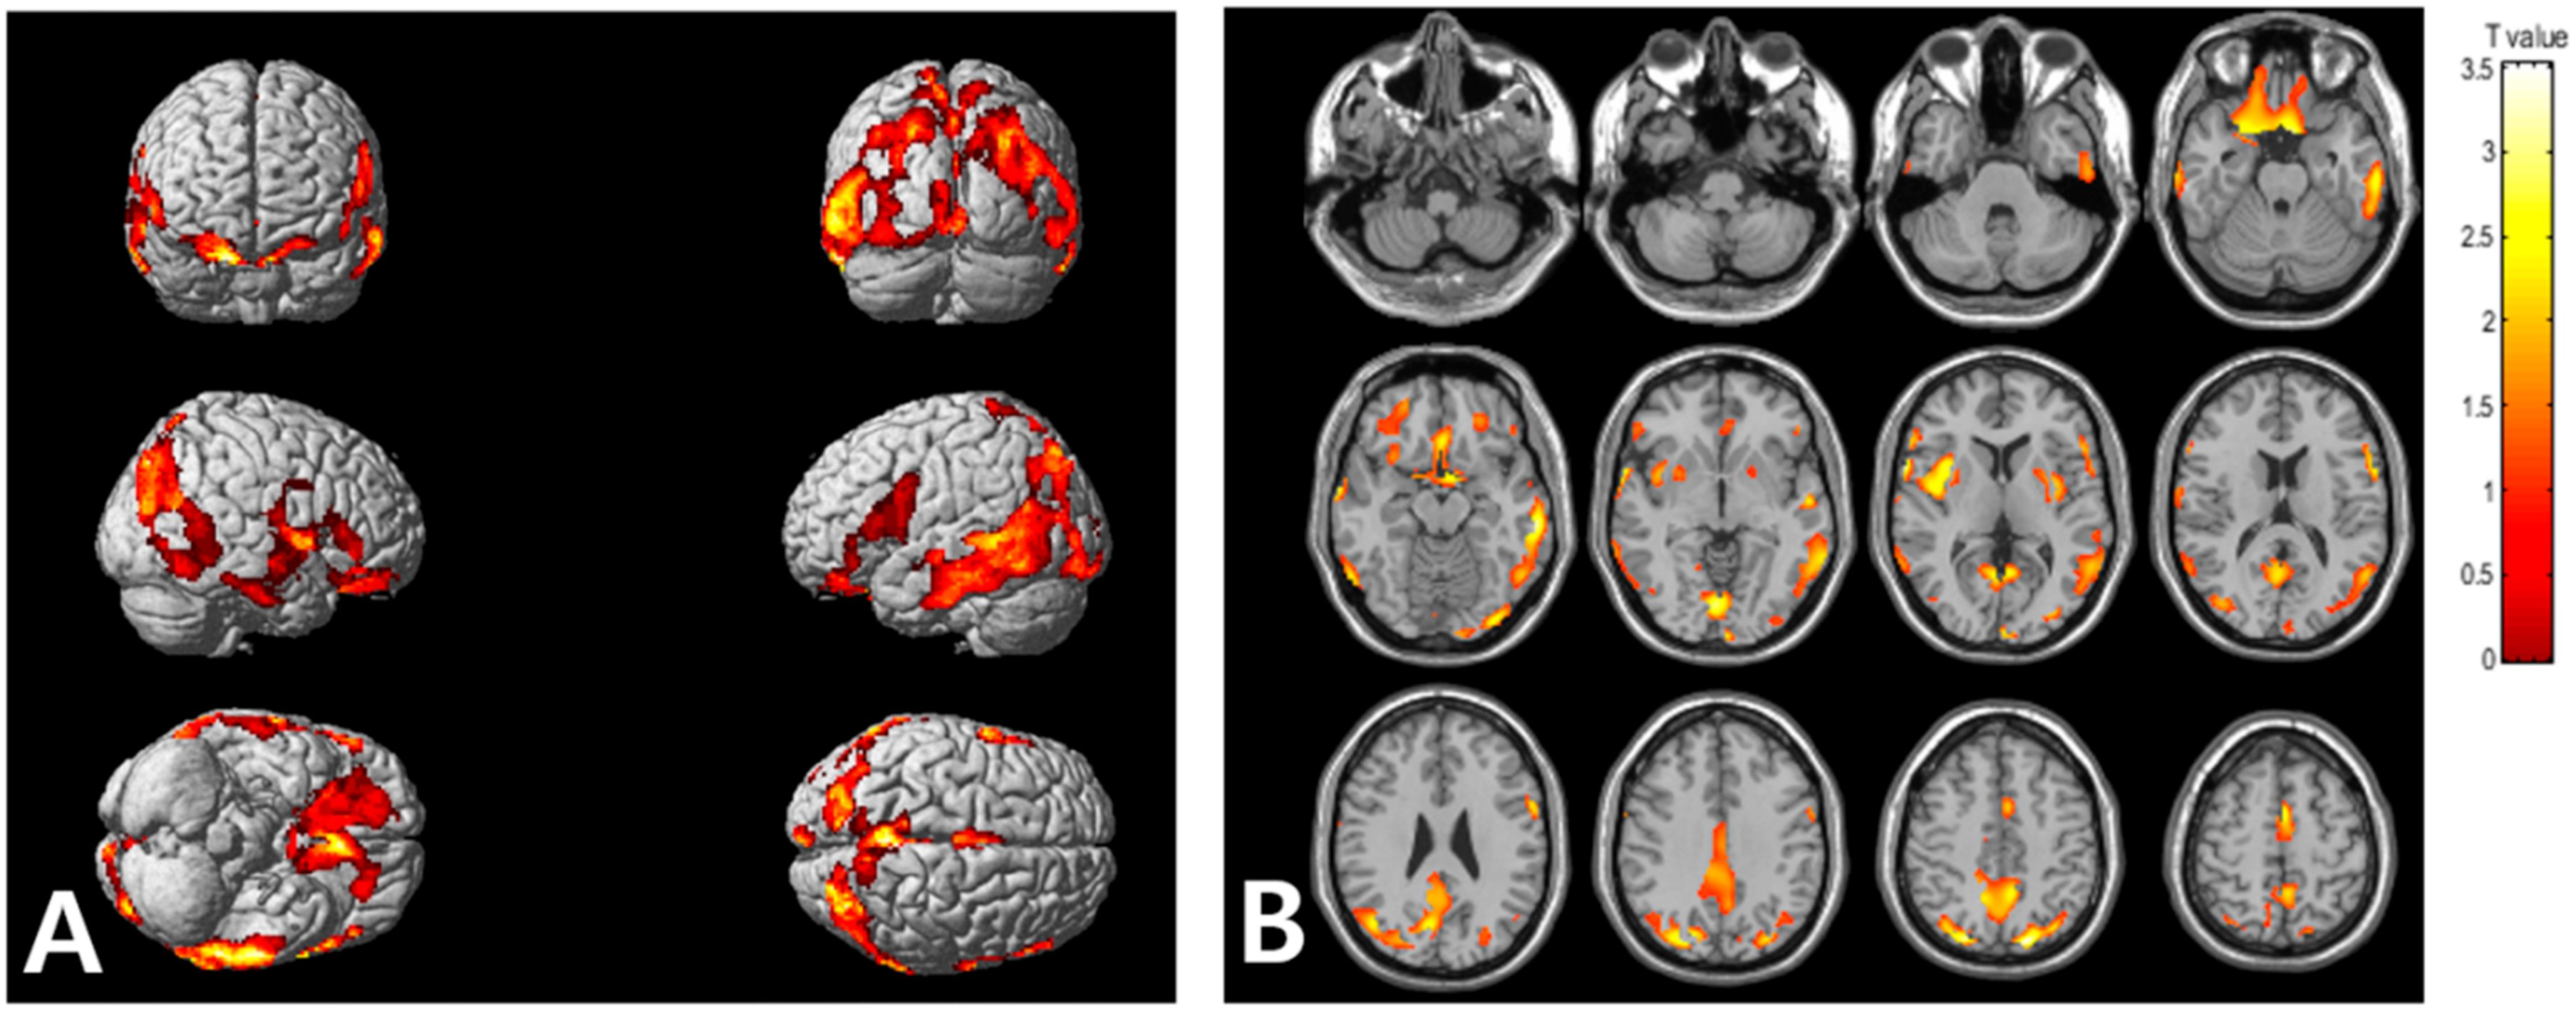

Statistical parametric mapping (SPM) analysis revealed that the high VAT metabolism group, compared with low VAT metabolism group, exhibited significantly high cerebral Aβ burden in the frontal, parietal, temporal, and occipital cortices, as well as in the insula (Figure 2). Table 3 summarizes the brain regions that showed increased cerebral Aβ burden in the high VAT metabolism group, compared with that in the low VAT metabolism group.

Figure 2.

Voxel-based comparison of cerebral Aβ burden between the high and low visceral adipose tissue (VAT) metabolism groups. The statistical parameter mapping t-maps were superimposed on the volume-rendered magnetic resonance imaging (MRI) (A) and T1-weighted template in the axial plane (B) for the high VAT metabolism group > low VAT metabolism group (p < 0.005, uncorrected at voxel-level, cluster size > 100 voxels).